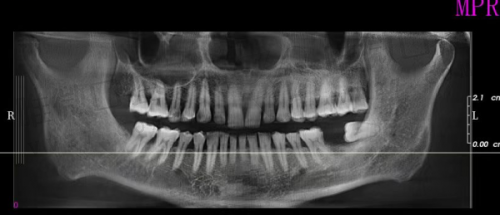

京植在术前诊断和评估上也特别用心,会结合拍片、口腔建模等方式进行全方面评估,确保种牙安心稳妥。